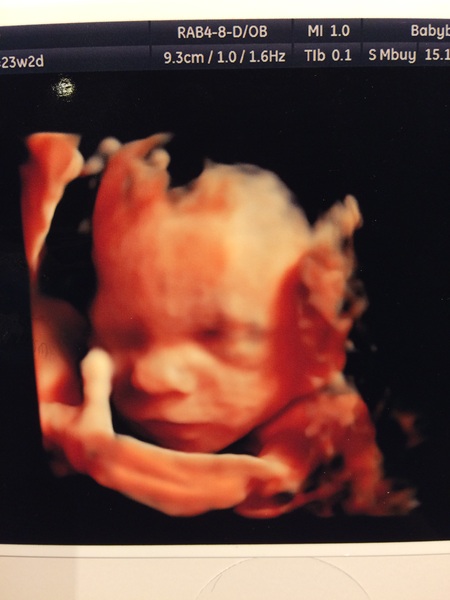

Went for a private gender scan today as they couldn't be sure at my 20 week scan. The lovely sonographer gave me a free glimpse in 3D! Our little girlSmile